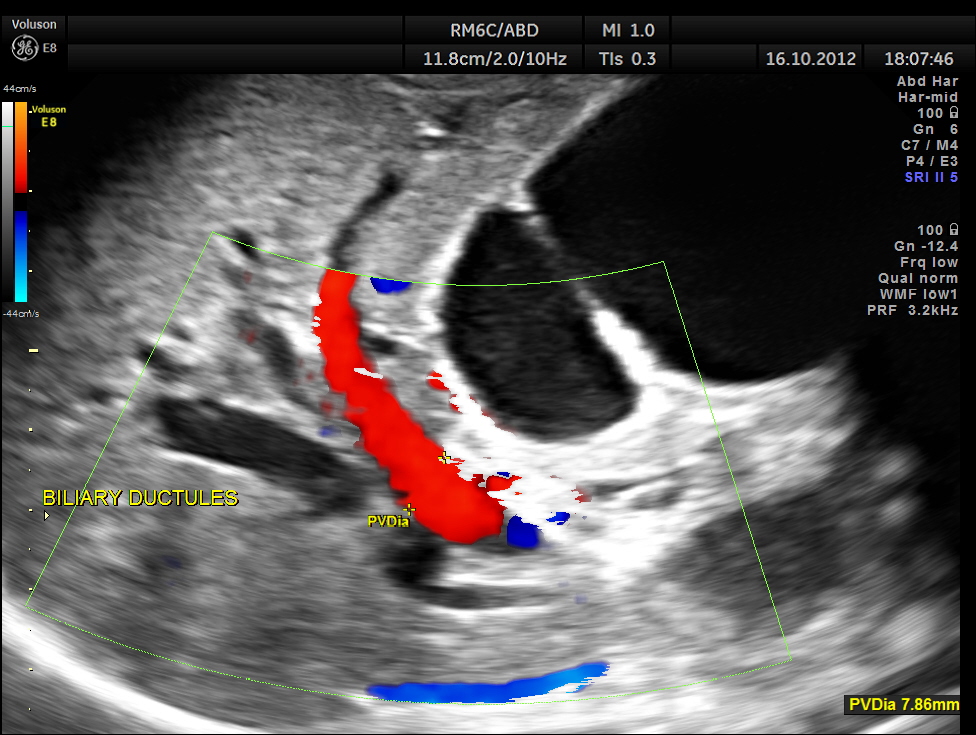

Courvoisier’s law (or Courvoisier syndrome, or Courvoisier’s sign or Courvoisier-Terrier’s sign) states that in the presence of an enlarged gallbladder which is nontender and accompanied with mild jaundice, the cause is unlikely to be gallstones. Usually, the term is used to describe the physical examination finding of the right-upper quadrant of the abdomen. This sign implicated possible malignancy of the gall bladder or pancreas and the swelling is unlikely due to gallstones.

This was a 55 year old man with history of jaundice and upper abdominal pain .